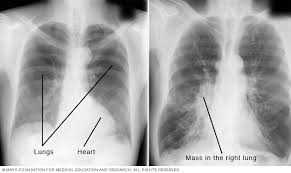

What Are The Symptoms Of Lung Cancer Mayo Clinic : Hundreds Of Mayo Clinic Staff Test Positive : • another pathological process with a similar clinical and radiological picture.. Lung cancer is also called as the lung's carcinoma, occurring when the cells growing in tissues of your lung are not controlled. Establishing the diagnosis of lung cancer: In most of the times, people who are affected with lung cancer may come to know only when cancer has become advanced. What are the symptoms of lung cancer? What are lung cancer symptoms and signs?

Anal Cancer Symptoms And Causes Mayo Clinic from www.mayoclinic.org Chest pain that is not just in one area of your chest. Lung cancer is a type of cancer that begins in the lungs. Find information about lung cancer, the deadliest cancer in the united states, from cleveland clinic. Diagnosing the lung cancer at an early stage would be helpful in the better treatment and. If needed, you may consult a doctor to get diagnosed with this in. When signs of the disease start to appear, they national cancer institute. Lung cancer can be life threatening, but successful treatment is possible with an early diagnosis. Staging allows the physician to fully understand the extent of the patient's cancer to determine treatment decisions.

Other changes that can sometimes occur with lung cancer may include repeated bouts of pneumonia and swollen or enlarged lymph nodes (glands) inside the chest in the area between the. • insensitivity of pathogens of pneumonia to antibacterial drugs; Some people have symptoms related to the lungs. Facts about the most common cancer symptoms and signs, which include lumps, blood in stool or urine, nonhealing sores, unexplained weight loss, fever, swollen what are 18 signs and symptoms of cancer? According to the mayo clinic, lung cancer is the leading cause of cancer death in the united states. Smoking is the number one cause of lung cancer. When signs of the disease start to appear, they national cancer institute. Common symptoms of lung cancer include: Diagnostics of lung cancer | latest medical news about the newest treatment methods in germany. Early lung cancer is usually symptomless, according to the mayo clinic. Lung cancer symptoms also resemble those of many other conditions, making it hard to. A persistent cough is the most common symptom of lung cancer and is found in around 50% of people at the time of diagnosis. You may not notice any symptoms of lung cancer ― many people don't.

Lung Ablation Specialty Group Overview Mayo Clinic from www.mayoclinic.org Find information about lung cancer, the deadliest cancer in the united states, from cleveland clinic. Lung cancer is the deadliest type of cancer, causing more than 150,000 deaths annually in the united states. Early lung cancer is usually symptomless, according to the mayo clinic. You may not notice any symptoms of lung cancer ― many people don't. Neurologic dysfunction can occur due to brain metastases or spinal cord compression. Lung cancer usually has no symptoms in its early stages. The symptoms of lung cancer range, like a chronic cough, can be easy to ignore or dismiss, but doing so can delay vital treatment. Many of the signs and symptoms can also be caused by other medical conditions but finding lung cancer early can mean that it's easier to treat.

Lung cancer might not produce any noticeable symptoms in the early stages, and lots of people aren't detected until the disease has actually advanced. The general prognosis of lung cancer is poor because doctors tend not to find the disease until it is at an advanced stage. Tobacco smoke contains many chemicals that are known to cause lung cancer. Learn more about common lung cancer symptoms. Symptoms of lung cancer can include a persistent cough, shortness of breath, coughing up blood, arm or chest pain, and unexplained weight loss.

Lung Cancer And Other Tobacco Related Diseases Nicotine Research Program Mayo Clinic Research from www.mayo.edu Diagnostics of lung cancer | latest medical news about the newest treatment methods in germany. Lung cancer may not produce symptoms that are noticeable in the early stages. What are the symptoms of lung cancer? Smoking is the number one cause of lung cancer. The general prognosis of lung cancer is poor because doctors tend not to find the disease until it is at an advanced stage. Lung cancer, also known as lung carcinoma, is a malignant lung tumor characterized by uncontrolled cell growth in tissues of the lung. Diagnosis and management of lung cancer, 3rd ed: Find information about lung cancer, the deadliest cancer in the united states, from cleveland clinic.